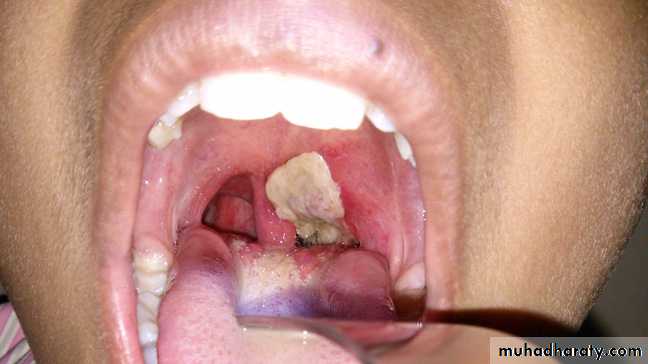

*Diphtheria toxin is absorbed into the mucous membranes and causes destruction of epithelium and a superficial inflammatory response.*The necrotic epithelium becomes embedded in exuding fibrin and red and white cells, so that a grayish “pseudomembrane” is— commonly over the tonsils, pharynx, or larynx.

*Enlarge of lymph nodes in the neck, and edema of the entire neck, with distortion of the airway.

Diphtheria can cause a swollen neck, sometimes referred to as a bull neck.

• When diphtheritic inflammation begins in the respiratory tract, sore throat and low-grade fever usually develop.• Prostration and dyspnea soon follow because of the obstruction caused by the membrane.

• This obstruction may even cause suffocation if not promptly relieved by intubation or tracheostomy.